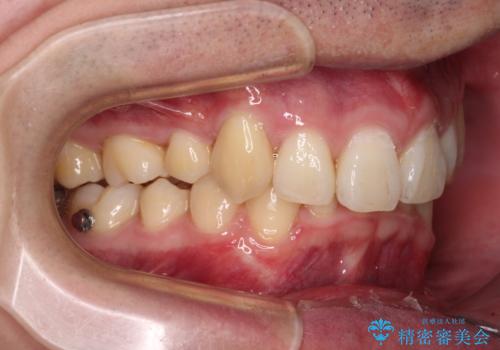

- 八重歯を気にして来院された患者様です。

顕著な上顎の八重歯とディープバイトであったため、上顎の左右第一小臼歯を抜歯することとしました。

犬歯歯根の位置や奥歯の咬み合わせから、ワイヤー装置での治療を強くおすすめいたしましたが、ご本人の強い希望により、妥協的な仕上がりとなることを了解いただき、インビザラインにて矯正治療を行うこととしました。

インビザライン単体で、左右ともに移動の難しい位置に歯根のある犬歯を整えるのは困難と判断し、補助装置を併用することとしました。

ディープバイトや奥歯の咬み合わせなど、インビザライン矯正では限界がありワイヤー装置での治療に及ばない仕上がりとなりました。

ただし、患者様としては八重歯や、それに伴う唇の閉じにくさが改善されたとのことで、納得いく状態での治療終了となりました。